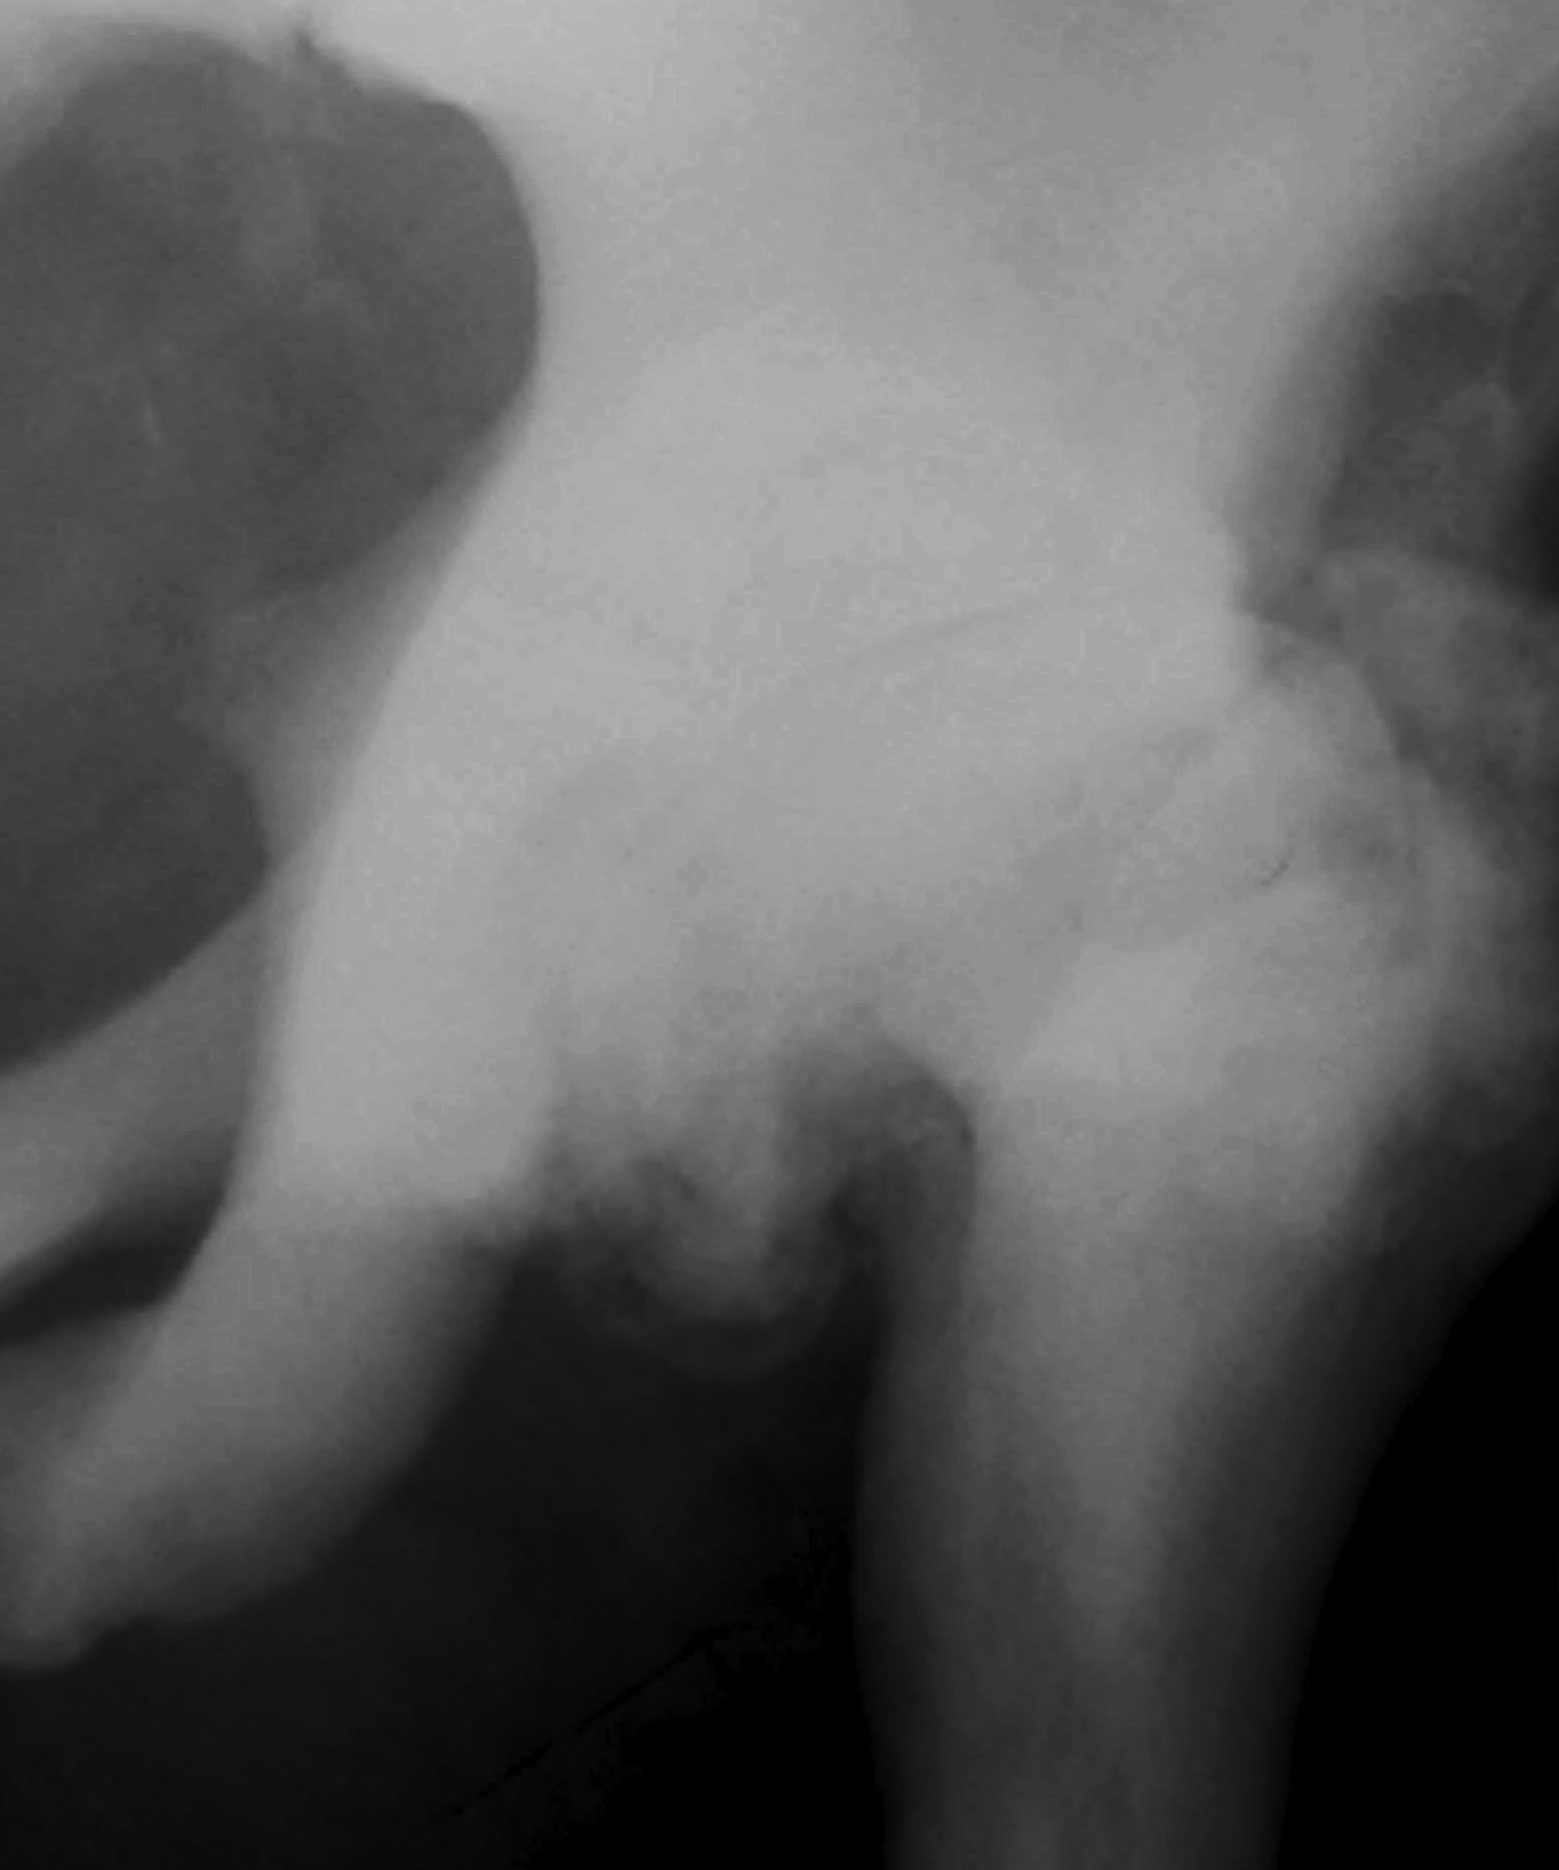

3. Hip

- coxa vara

Erlenmeyer flask deformity

- widened club like metaphysis

- in children